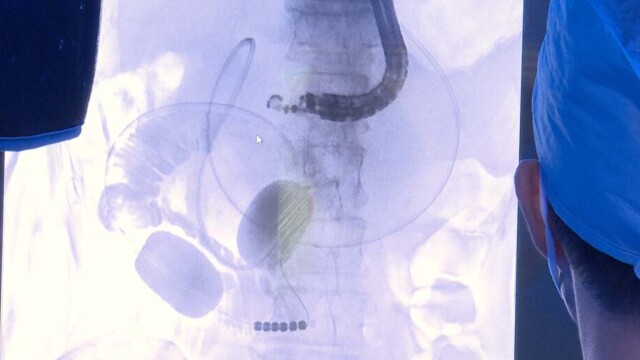

New Approach to Treating Pancreatic Disease